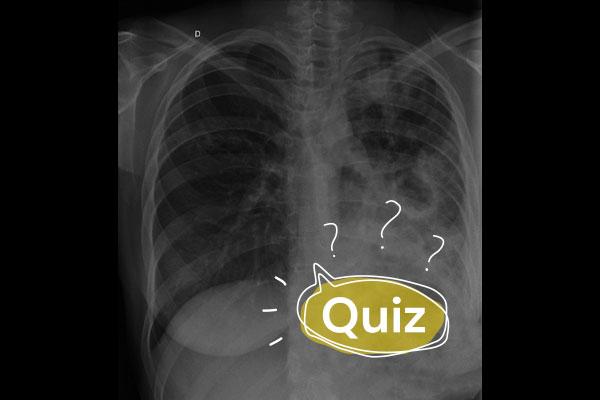

Paciente RRD, sexo feminino, 69 anos, HAS e dislipidemia, história de tuberculose pulmonar com tratamento completo e cura clínico-laboratorial há dois anos, comparece ao pronto-socorro com queixa de febre aferida (39,1°C), tosse produtiva e leve dispneia, de início há seis dias e com piora progressiva. Ausculta pulmonar com estertores crepitantes em base do hemitórax esquerdo, com o raio-x de tórax apresentando faixas de atelectasias e bandas fibroparenquimatosas no ápice do lobo superior direito e consolidação em 1/3 inferior do hemitórax esquerdo. Refere quadro semelhante há três meses, com melhora após uso de antibioticoterapia, momento no qual, dentre outros exames, fora solicitado BAAR, TRM-TB (Xpert® MTB/RIF Ultra) e cultura do escarro devido ao passado de tuberculose. Trouxe consigo ao pronto-socorro os resultados desses exames coletados há três meses, com os seguintes achados:

Levando-se em conta a história clínica, exame físico e resultado de exames complementares, o quadro mais provável é de:

AErro laboratorial

BMicobacteriose não tuberculosa (MNT)

CPneumonia bacteriana

DRecidiva de tuberculose